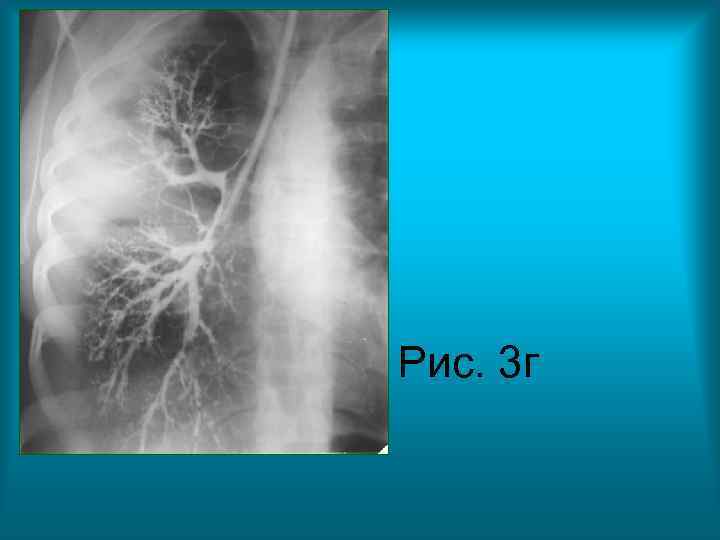

• Рис. 3 в. , Рис. 3 г. Контрастное исследование бронхиального дерева правого легкого в прямой проекции (бронхография). Определяется сужение и неравномерное заполнение контрастным веществом сегментарного и субсегментарных бронхов третьего сегмента верхней доли правого легкого. Бронхи средней доли правого легкого проходимы, веточки их сближены, но не деформированы.

Рис. 3 г